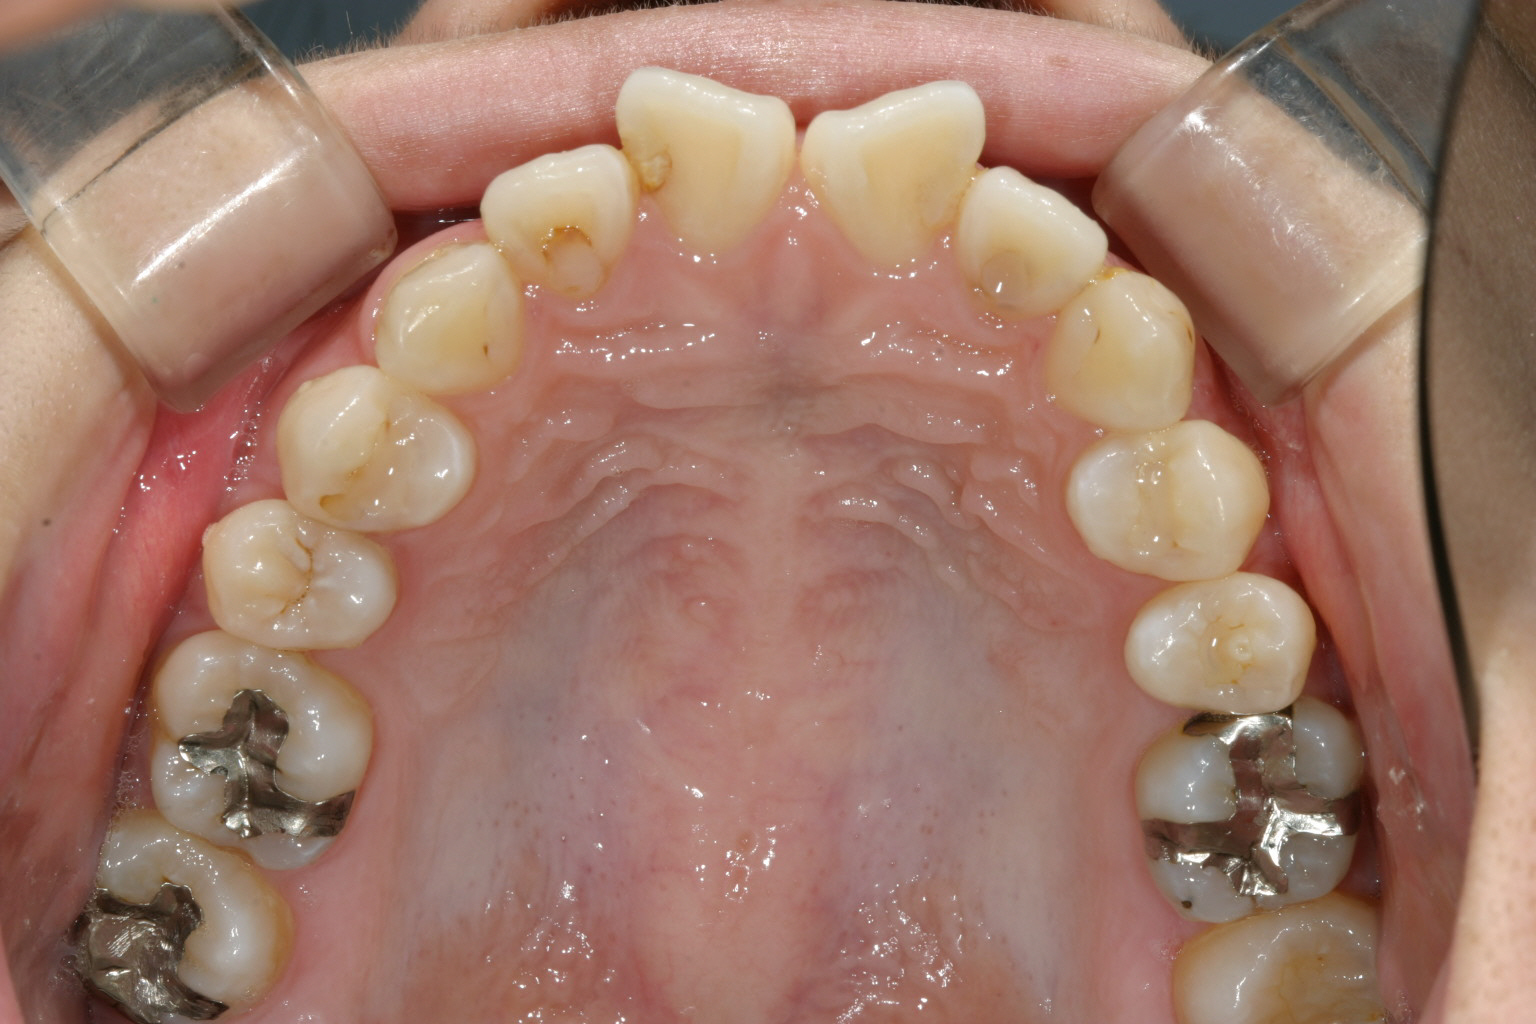

前歯かなり捻転してますね~

凄いでっぱです。 特に歯が捻転してますから余計に出っ歯感が増します。